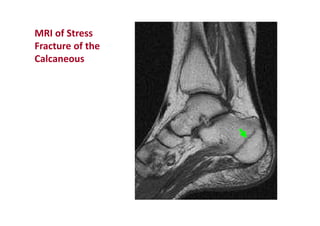

MRI of Stress

Fracture of the

Calcaneous